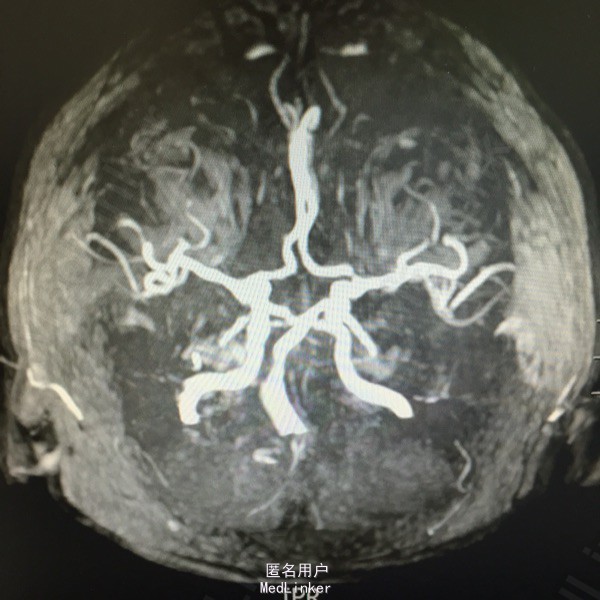

头痛伴视物双影5天。既往高血压、糖尿病、脑梗死。该患于入院前5日无明显诱因出现视物双影,偶伴头痛,不伴有恶心、呕吐,无视物旋转,无吞咽困难,病程中无肢体活动障碍,无言语不清,无意识障碍及尿便失禁。曾有中耳炎病史,伴有听力减退,曾于入院前3日在眼科医院激光治疗眼底出血。为求进一步诊治而来我院。

查体:神清语利,左眼内收受限,鼻唇沟对称,伸舌居中,双耳听力减退,肌力肌张力正常,双下肢病理症(-)颈强(-)。

诊断:脑梗死、高血压、2型糖尿病、高脂血症、中耳炎 治疗:营养神经、改善循环、神经生长因子、降脂、抗炎对症治疗。

患者住院14天,出院时视物双影基本消失,无头痛主诉。是否可以给出更详细的诊断?